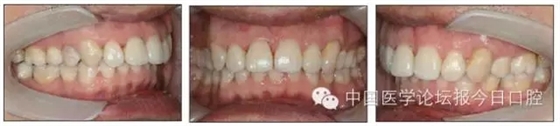

本病例為慢性牙周炎致前牙漂移、深覆(牙合)患者。本病例采用無托槽隱形矯治技術進行治療。無托槽隱形矯治器具有可摘戴、便于口腔衛(wèi)生維護和牙周治療的優(yōu)點,更適合于伴有牙周炎的錯(牙合)畸形患者的治療。 患者男,48歲,前牙有縫、前突求診。 患者面部對稱,側(cè)面觀上頜前突,下頜后縮。 口內(nèi)情況:恒牙列,24、34、44缺失,磨牙Ⅲ類關系,上牙列散隙,上前牙扇形漂移。前牙深覆(牙合)、深覆蓋??谇恍l(wèi)生較差,11與12間牙齦乳頭紅腫,多個牙探診有牙周袋形成,11松動Ⅰ度,余切牙松動(-),患者面像及口內(nèi)像如圖1、2所示。 圖1 治療前面像 圖2 治療前口內(nèi)像 全口曲面體層片(圖3)顯示,患者全牙列牙槽骨吸收;根尖片(圖4)示11近中牙槽骨角形吸收已達根尖1/3,21牙槽骨嵴頂吸收至根1/2,23牙槽骨近中骨板角形吸收至根1/2。磨牙區(qū)骨嵴頂吸收3mm。治療前頭顱側(cè)位片見圖3,治療前ODS模型見圖5。 圖4 治療前根尖片 圖5 治療前ODS模型 牙型:安氏Ⅲ類。骨型:Ⅱ類。面型:上頜前突,下頜后縮。 問題列表為:①上牙列間隙;②上切牙病理性牙移位;③前牙深覆(牙合)、深覆蓋;④24、34、44缺失;⑤慢性牙周炎。 矯治目標包括:①排齊牙列,關閉牙列間隙;②改善前牙深覆(牙合)、深覆蓋;③改善牙周狀況。 矯治設計有:①牙周基礎治療與維護。②壓低、內(nèi)收上切牙,關閉上牙列間隙。③壓低下切牙,伸長下后牙,整平Spee曲線,改善前牙覆(牙合)、覆蓋。 患者進行全口齦上潔治、齦下刮治,口腔衛(wèi)生宣教,并按牙周醫(yī)師的要求,每2~3個月行牙周檢查與治療。 牙周基礎治療結(jié)束3個月,開始隱形矯治。于14、25、35、36、45、46上粘接附件(圖6),于16、26(牙合)面粘接(牙合)墊。 圖6 ODS設計附件粘接圖示 矯治過程中注意(牙合)墊是否脫落或磨損,及時修補。 注意上前牙內(nèi)收時有無咬合干擾,及時調(diào)(牙合)。下頜前磨牙伸長到位后,磨除16、26(牙合)墊。 下頜佩戴第24步矯治器時,分別在36、37、46、47的頰、舌側(cè)粘接舌扣,矯治器上預留伸長空間,用3/16英寸、3.5盎司皮圈牽引,輔助伸長下磨牙(圖7)。 患者共戴用矯治器上頜32步,下頜26步。 矯治后,牙列間隙關閉,面型及覆(牙合)覆蓋改善。11根尖片(圖8)顯示,治療后較治療前,牙周支持組織增加,牙槽骨角形吸收區(qū)水平向縮小0.3mm,垂直向縮小0.6mm。11松動Ⅰ度,余切牙無松動。 圖8 治療后根尖片 圖9 治療后口內(nèi)像 圖10 治療后X線檢查 圖11 治療后ODS模型 正畸-牙周聯(lián)合治療對于牙周組織的影響 多學科綜合治療牙周炎患者不再是正畸治療的禁忌證。良好的牙周治療為正畸治療中的牙齒移動打下堅實基礎,而正畸治療排齊牙齒、去除(牙合)干擾,有利于牙周健康。 牙周炎患者的正畸治療必須在牙周炎癥得到控制后才能進行,否則,菌斑會隨著牙齒的移動,特別是壓低而使牙周炎癥加重。牙周炎的正確診斷、牙周炎癥控制、正畸治療中和治療后的認真維護是治療成功的關鍵。根據(jù)臨床需要,一般每2~4周做一次潔治,每3個月進行牙周評估,同時患者必須進行非常良好的日??谇恍l(wèi)生維護。 固定矯治器使得牙周檢查、潔治和日??谇恍l(wèi)生維護變得困難,隱形矯治器可自行摘戴,便于患者日常維護和牙周治療,節(jié)約時間,提高菌斑控制效果。 有臨床研究表明,對于存在(牙合)創(chuàng)傷,伴有角形吸收的患牙,經(jīng)過牙周翻瓣手術控制住牙周炎癥后,使用正畸輕力壓低患牙,可以改善牙槽骨吸收的程度,并獲得一定程度的牙周新附著。本病例切牙壓低后,原來的牙槽骨吸收有改善。 病理性牙移位 病理性牙移位(PTM)在重度牙周炎患者中的發(fā)生率為30%~50%,且常見于上前牙區(qū)。其主要由于牙周支持組織喪失尤其是骨組織的丟失,咬合因素(如后牙缺失、前牙深覆牙合、牙合創(chuàng)傷等),頰舌唇肌力量不平衡及牙周和根尖周組織炎癥所致,是牙周炎患者要求正畸治療的主要原因之一。 PTM須通過正畸、牙周聯(lián)合,有時須配合修復才能達到理想的治療效果。正畸治療通常是壓低牙齒,臨床研究表明,牙周手術配合正畸壓低可以產(chǎn)生新附著,有利于PTM牙周組織的恢復。 本病例右上中切牙牙槽骨角形吸收,在盡量保證治療前后根尖片投照角度一致的情況下,以鄰牙作為校準,在根尖片上對治療前后的骨量進行評價,治療后牙槽骨角形吸收區(qū)水平向縮小0.3 mm,垂直向縮小0.6mm。盡管根尖片并不能說明骨量改變,但從影像學上能看到骨吸收區(qū)域有所減小。 無托槽隱形矯治器矯治牙周病的優(yōu)勢 無托槽隱形矯治器具有可摘戴、便于口腔衛(wèi)生維護和牙周治療的優(yōu)點,更適合于伴有牙周炎的錯(牙合)患者的治療;同時,無托槽隱形矯治器佩戴后具有牙弓夾板和(牙合)板的作用,可有效減少側(cè)向力,有利于牙周的恢復和減輕牙齒松動;由于無托槽隱形矯治器的設計是在三維數(shù)字模型上進行的,每個矯治器移動牙齒的數(shù)量和每個牙齒的移動距離可以得到量化控制,因而可以根據(jù)患者牙槽骨水平和對矯治力的耐受情況個性化設計矯治力,并且可以根據(jù)矯治中牙齒移動情況調(diào)整后續(xù)矯治器的設計。 有關磨牙伸長 單純使用無托槽隱形矯治器同步伸長后牙比較困難。該病例先使用磨牙(牙合)墊打開咬合,通過矯治器伸長前磨牙,在前磨牙建立咬合后,磨除磨牙上的(牙合)墊,通過輔助牽引伸長磨牙,最終達到伸長后牙、整平Spee曲線的目的。 史真,主任醫(yī)師,現(xiàn)任北京黃寺整形外科醫(yī)院口腔科主任,第四軍醫(yī)大學口腔正畸學碩士,為世界正畸醫(yī)師聯(lián)盟(WFO)會員、全軍口腔醫(yī)學專業(yè)委員會委員、中華口腔正畸專業(yè)委員會委員、中華醫(yī)學美學與美容學會齒科美容學組成員、北京口腔醫(yī)學會兒童口腔專業(yè)委員會常務委員、北京口腔醫(yī)學會正畸專業(yè)委員會委員、《中華醫(yī)學美學與美容》雜志審稿專家,是我國最早開展無托槽隱形矯治技術的口腔醫(yī)師之一。